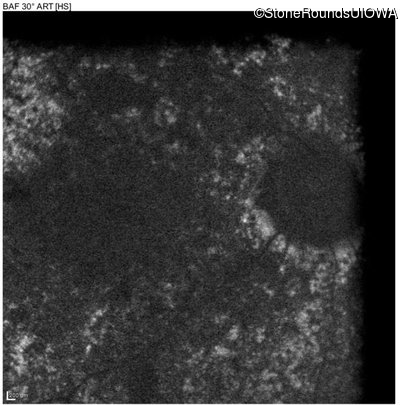

Blue Autofluorescence - Right - 20/500 sc

Exemplar

Blue Autofluorescence - Left - 20/1000 sc